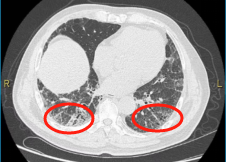

▲2023年胸部CT显示,双肺间质性肺炎

(画圈处)病变较前增多、进展